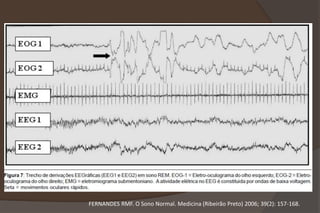

 Variáveis Fisiológicas:

 EEG;

 EOG;

 EMG submentoniano;

 Padrões fundamentais do sono:

 Sono NREM;

 Sono REM;

FERNANDES RMF. O Sono Normal. Medicina (Ribeirão Preto) 2006; 39(2): 157-168.